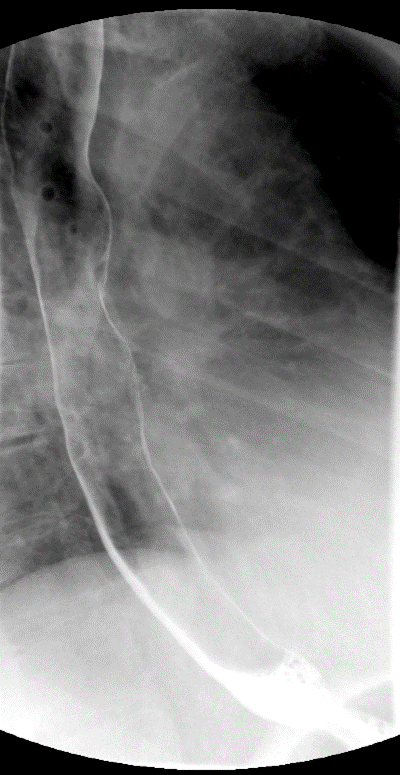

- The technologist will obtain a scout radiograph(s) to include the chest and upper abdomen to determine the location of the surgical chain sutures or surgical staples

(key image 1).

- The esophagogastric anastomosis is usually located at the level of the aortic arch or just below it.